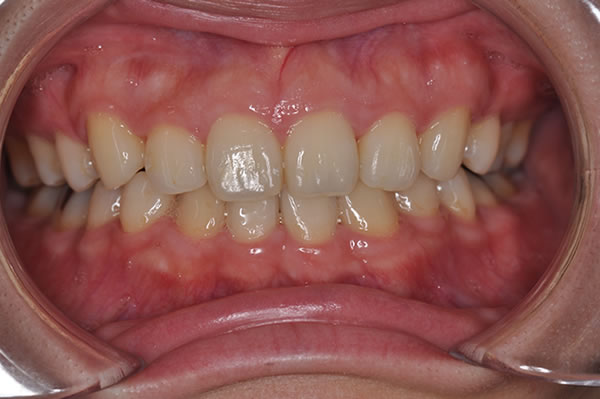

上顎前突症の治療例

上顎前突症(出っ歯)の矯正症例 ケース02

| 治療前(初診) | 治療後 | |